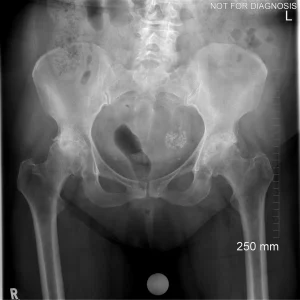

A total hip replacement (also called total hip arthroplasty) is a surgical procedure in which a damaged or worn hip joint is replaced with artificial components. The hip is a ball-and-socket joint, meaning the ball at the top of the thigh bone sits in a socket on the pelvis. During surgery, the damaged ball (femoral head) is replaced with a metal or ceramic ball attached to a stem, and the damaged socket is replaced with a metal cup lined with plastic, ceramic, or metal.